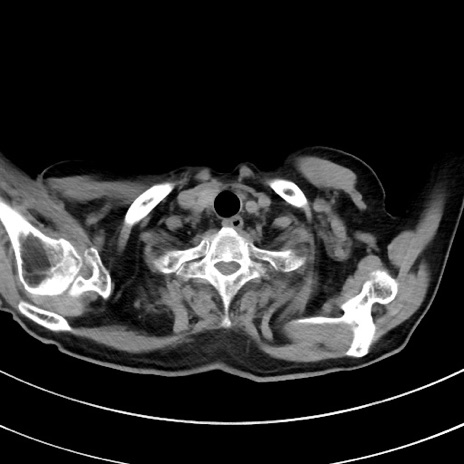

症例33(横断像)

【症例】70歳代 女性

【主訴】心窩部痛

【現病歴】延髄病変の精査・加療にて神経内科入院中。本日より心窩部痛あり。

【身体所見】右下腹部を中心に圧痛と反跳痛あり。

【データ】WBC 10900、CRP 0.02